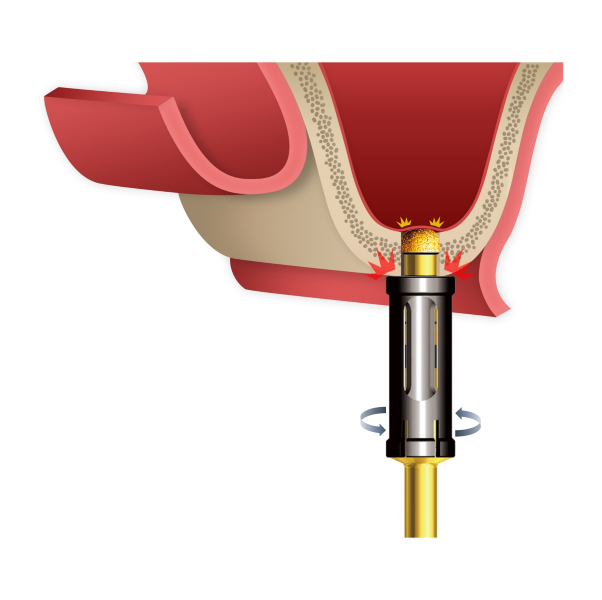

Crestal Drill

Enables controlled and predictable access to the sinus floor with minimal apical pressure.Designed to support precise drilling depth control while reducing the risk of sinus membrane perforation.

Crestal Approach

Crestal Approach -